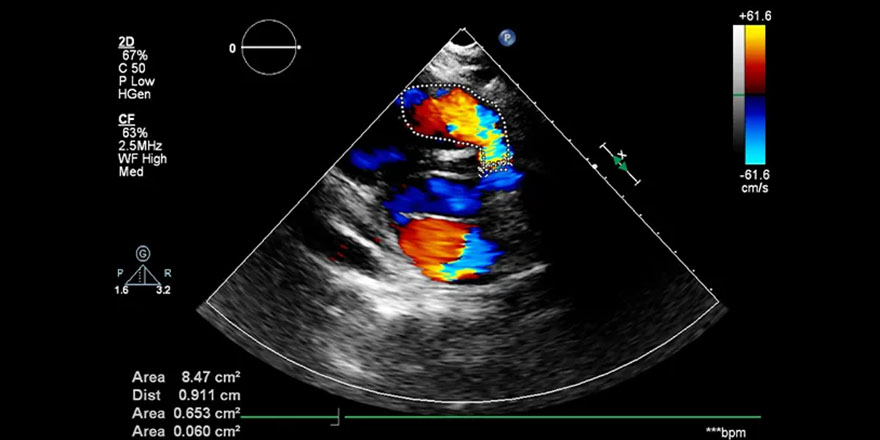

در واقع، سونوگرافی داپلر عروق مغز، راحت‌ترین راه برای نظارت بر تغییرات عروقی در پاسخ به حوادث حاد عروق مغزی در بیمار می‌باشد.